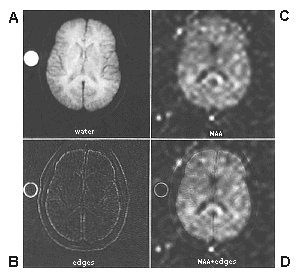

Figure 3.

Co-registration of structural MRI and proton MRS images, acquired in the same scan session from a healthy young control.  Left column (upper) illustrates unprocessed axial water-based structural image, and (lower) edge-detected version.  Right column (upper) illustrates proton inversion recovery MRS image of n-acetylaspartic acid (NAA) distribution in the axial plane, and (lower) a linear combination of NAA distribution and structural edges providing neuroanatomic definition without obscuring spectroscopic data.  Figure provided courtesy of Daniel Spielman, Department of Radiology, Stanford University.